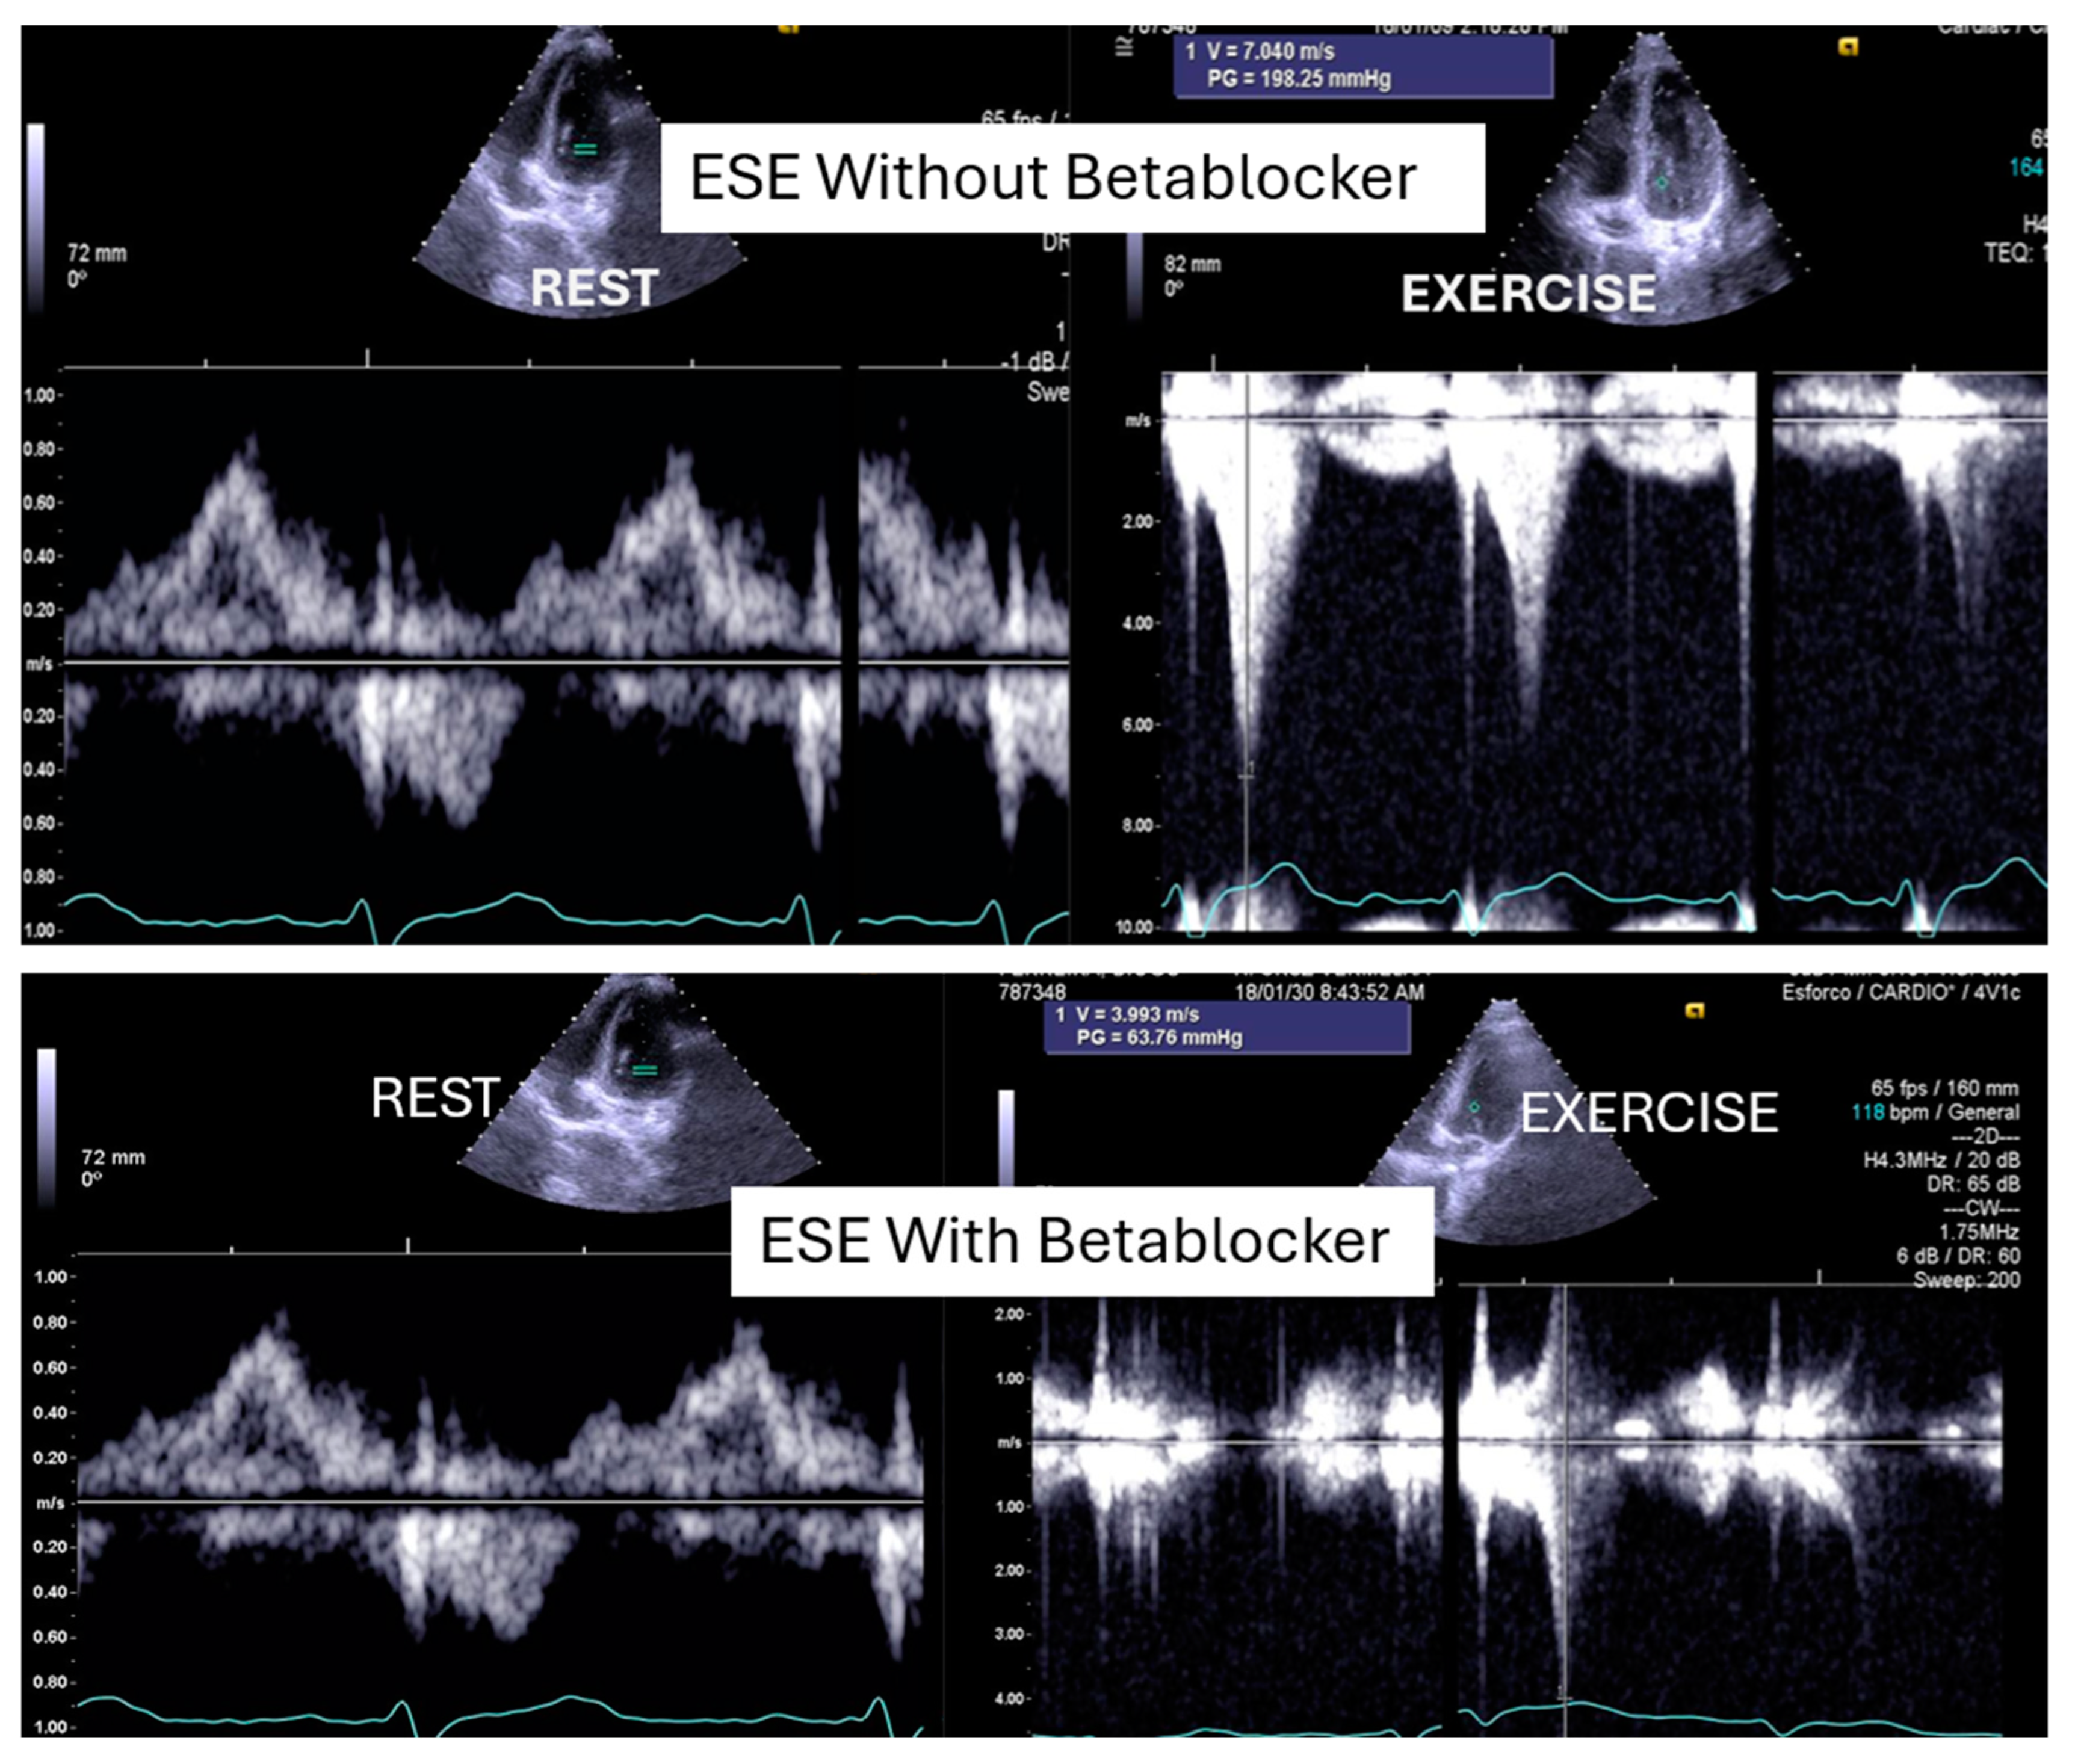

- Cotrim, C.; Palinkas, E.D.; Cotrim, N. The Importance of Left Ventricular Outflow Tract and Mid-Ventricular Gradients in Stress Echocardiography: A Narrative Review. J. Clin. Med. 2023, 12, 5292. [Google Scholar] [CrossRef] [PubMed]

- Cotrim, C.; Picano, E. Step G for Gradients in Stress Echocardiography. In Stress Echocardiography; Picano, E., Ed.; Springer: Cham, Switzerland, 2023. [Google Scholar] [CrossRef]

- Cotrim, C.; Almeida, A.R.; Miranda, R.; Almeida, A.G.; Cotrim, H.; Picano, E.; Carrageta, M. Stress-induced intraventricular gradients in symptomatic athletes during upright exercise continuous wave Doppler echocardiography. Am. J. Cardiol. 2010, 106, 1808–1812. [Google Scholar] [CrossRef] [PubMed]

- Cotrim, C.; Lopes, L.R.; Almeida, A.R.; Miranda, R.; Ana, A.G.; Cotrim, H.; Andrade, J.P.; Carrageta, M. Efficacy of beta-blocker therapy in symptomatic athletes with exercise-induced intra-ventricular gradients. Cardiovasc. Ultrasound. 2010, 8, 38. [Google Scholar] [CrossRef] [PubMed]

- Cabrera-Bueno, F.; García-Pinilla, J.M.; Gómez-Doblas, J.J.; Montiel-Trujillo, A.; Rodríguez-Bailón, I.; de Teresa-Galván, E. Beta-blocker therapy for dynamic left ventricular outflow tract obstruction induced by exercise. Int. J. Cardiol. 2007, 117, 222–226. [Google Scholar] [CrossRef]

- Al-Nasser, F.; Duncan, A.; Sharma, R.; O’Sullivan, C.; Coats, A.J.S.; Anker, S.D.; Henein, M.Y. Beta-blocker therapy for dynamic left-ventricular outflow tract obstruction. Int. J. Cardiol. 2002, 86, 199–205. [Google Scholar] [CrossRef]